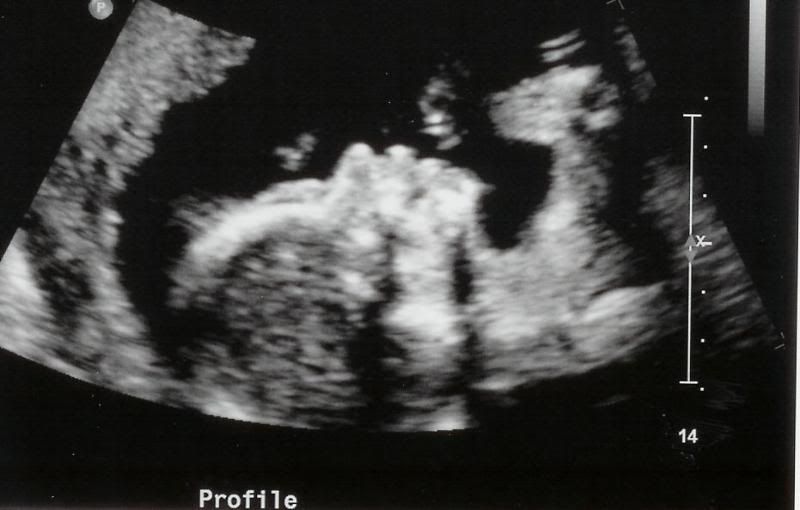

The Ultrasound this morning went wonderfully. The gender of the baby was written down on a card and sealed up without me looking! Also included is a picture of the baby. The U/S technician was so wonderful to me when I told him you were deployed that he printed out 5 pictures for me. You remember with Autumn, they would only give you one. The baby's heart rate measured anywhere from 139 to 144 beats per minute. I saw the head, spine, eye sockets, nose, lips, hands, kidneys, stomach, legs, feet, arms and the most astonishing was the heart. All four chambers beating beautifully. The technician seemed to spend a lot of time around the brain area and I don't know if that means anything or not because they spent a lot of time looking around Autumn's heart last time and this time, not so much. I will get to review the results of my U/S with my doctor in two weeks. Here are the pictures:

Profile

Profile again. Someone (Angie I think) made mention that it looks like hair on the head which made me laugh out loud!! Wouldn't that be nice if New Human really did have some hair! Travis says the baby looks like Autumn and I quite agree.